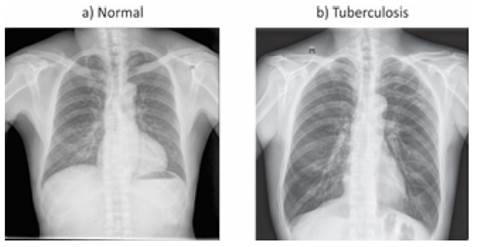

En el presente estudio se trabajó con dos conjuntos de datos publicados en la comunidad de ciencias de datos KAGGLE por Rahman et al. 11 y Jaeger et al. 12, al combinar los dos conjuntos de datos dan un total de 7662 imágenes de radiografías del tórax de pacientes anonimizados, el objetivo de unificar los dos datasets es de tener una mayor variabilidad en los datos, al momento de entrenar los algoritmos puedan generalizar adecuadamente ante diferentes fuentes de imágenes en la etapa de validación y test. Se realizó un análisis de cada imagen para descartar las que contaban con ruido; es decir, no correspondía a una de las clases, eran ilegibles, tenían textos o cuadros blancos o negros sobrepuestos, mal posicionamiento entre otros aspectos que hacían que estas imágenes no cumplieran las características de cada clase del dataset. Después de la depuración de los datos inválidos que podrían generar ruido al momento de entrenar los algoritmos, quedó un dataset de un total de 5748 imágenes, 2905 imágenes de pacientes sanos y 2843 imágenes de pacientes con tuberculosis. El dataset se dividió en dos conjuntos, el conjunto de entrenamiento con el 80% y el conjunto de test con el 20% del total. Del total de los datos del entrenamiento se divido nuevamente en datos para entrenar y datos para la validación, en este caso del total de los datos de entrenamiento un 20% se destinará para la validación cruzada en la etapa de entrenamiento. Se puede ver una muestra en la Figura 1.